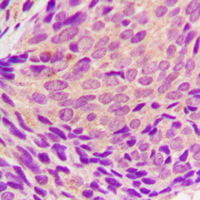

Immunohistochemical analysis of SYK (Phospho-Y323) staining in human breast cancer formalin fixed paraffin embedded tissue section. The section was pre-treated using heat mediated antigen retrieval with sodium citrate buffer (pH 6.0). The section was then incubated with the antibody at room temperature and detected using an HRP conjugated compact polymer system. DAB was used as the chromogen. The section was then counterstained with haematoxylin and mounted with DPX. -